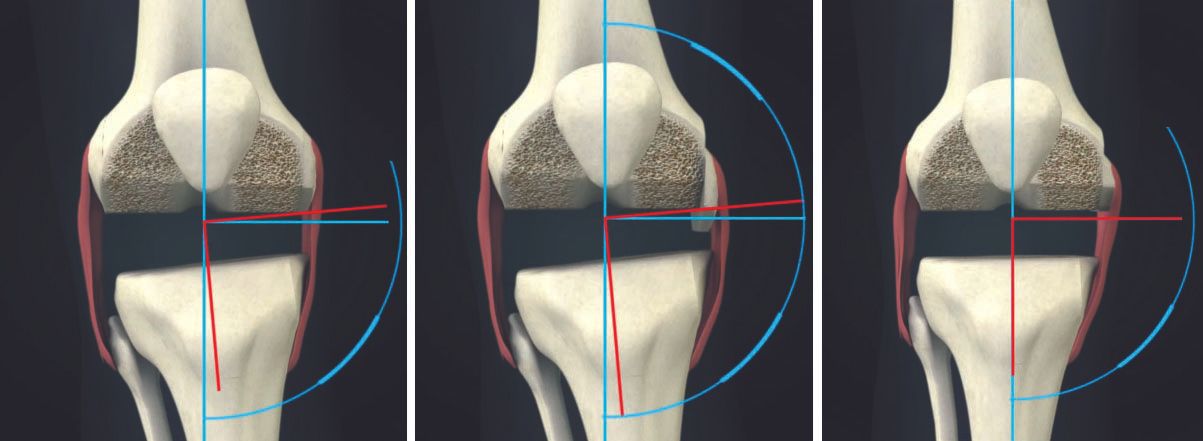

6. The proximal tibial cut affects both flexion and extension gaps equally; the distal femoral cut affects only the extension gap. The posterior femoral cut affects the flexion gap; the anterior femoral cut affects patellar tracking.(Figs 2, 3)

The author has performed over 12000 total knee replacements, over 6000 with computer navigation and has made several observations which are published in scientific studies 1-12. Here is the method followed which has satisfactorily achieved alignment and balance without requiring release of the superficial medial collateral ligament2 and without using constrained implants (only posterior cruciate substituting designs have been used in almost all cases)(Fig 1).